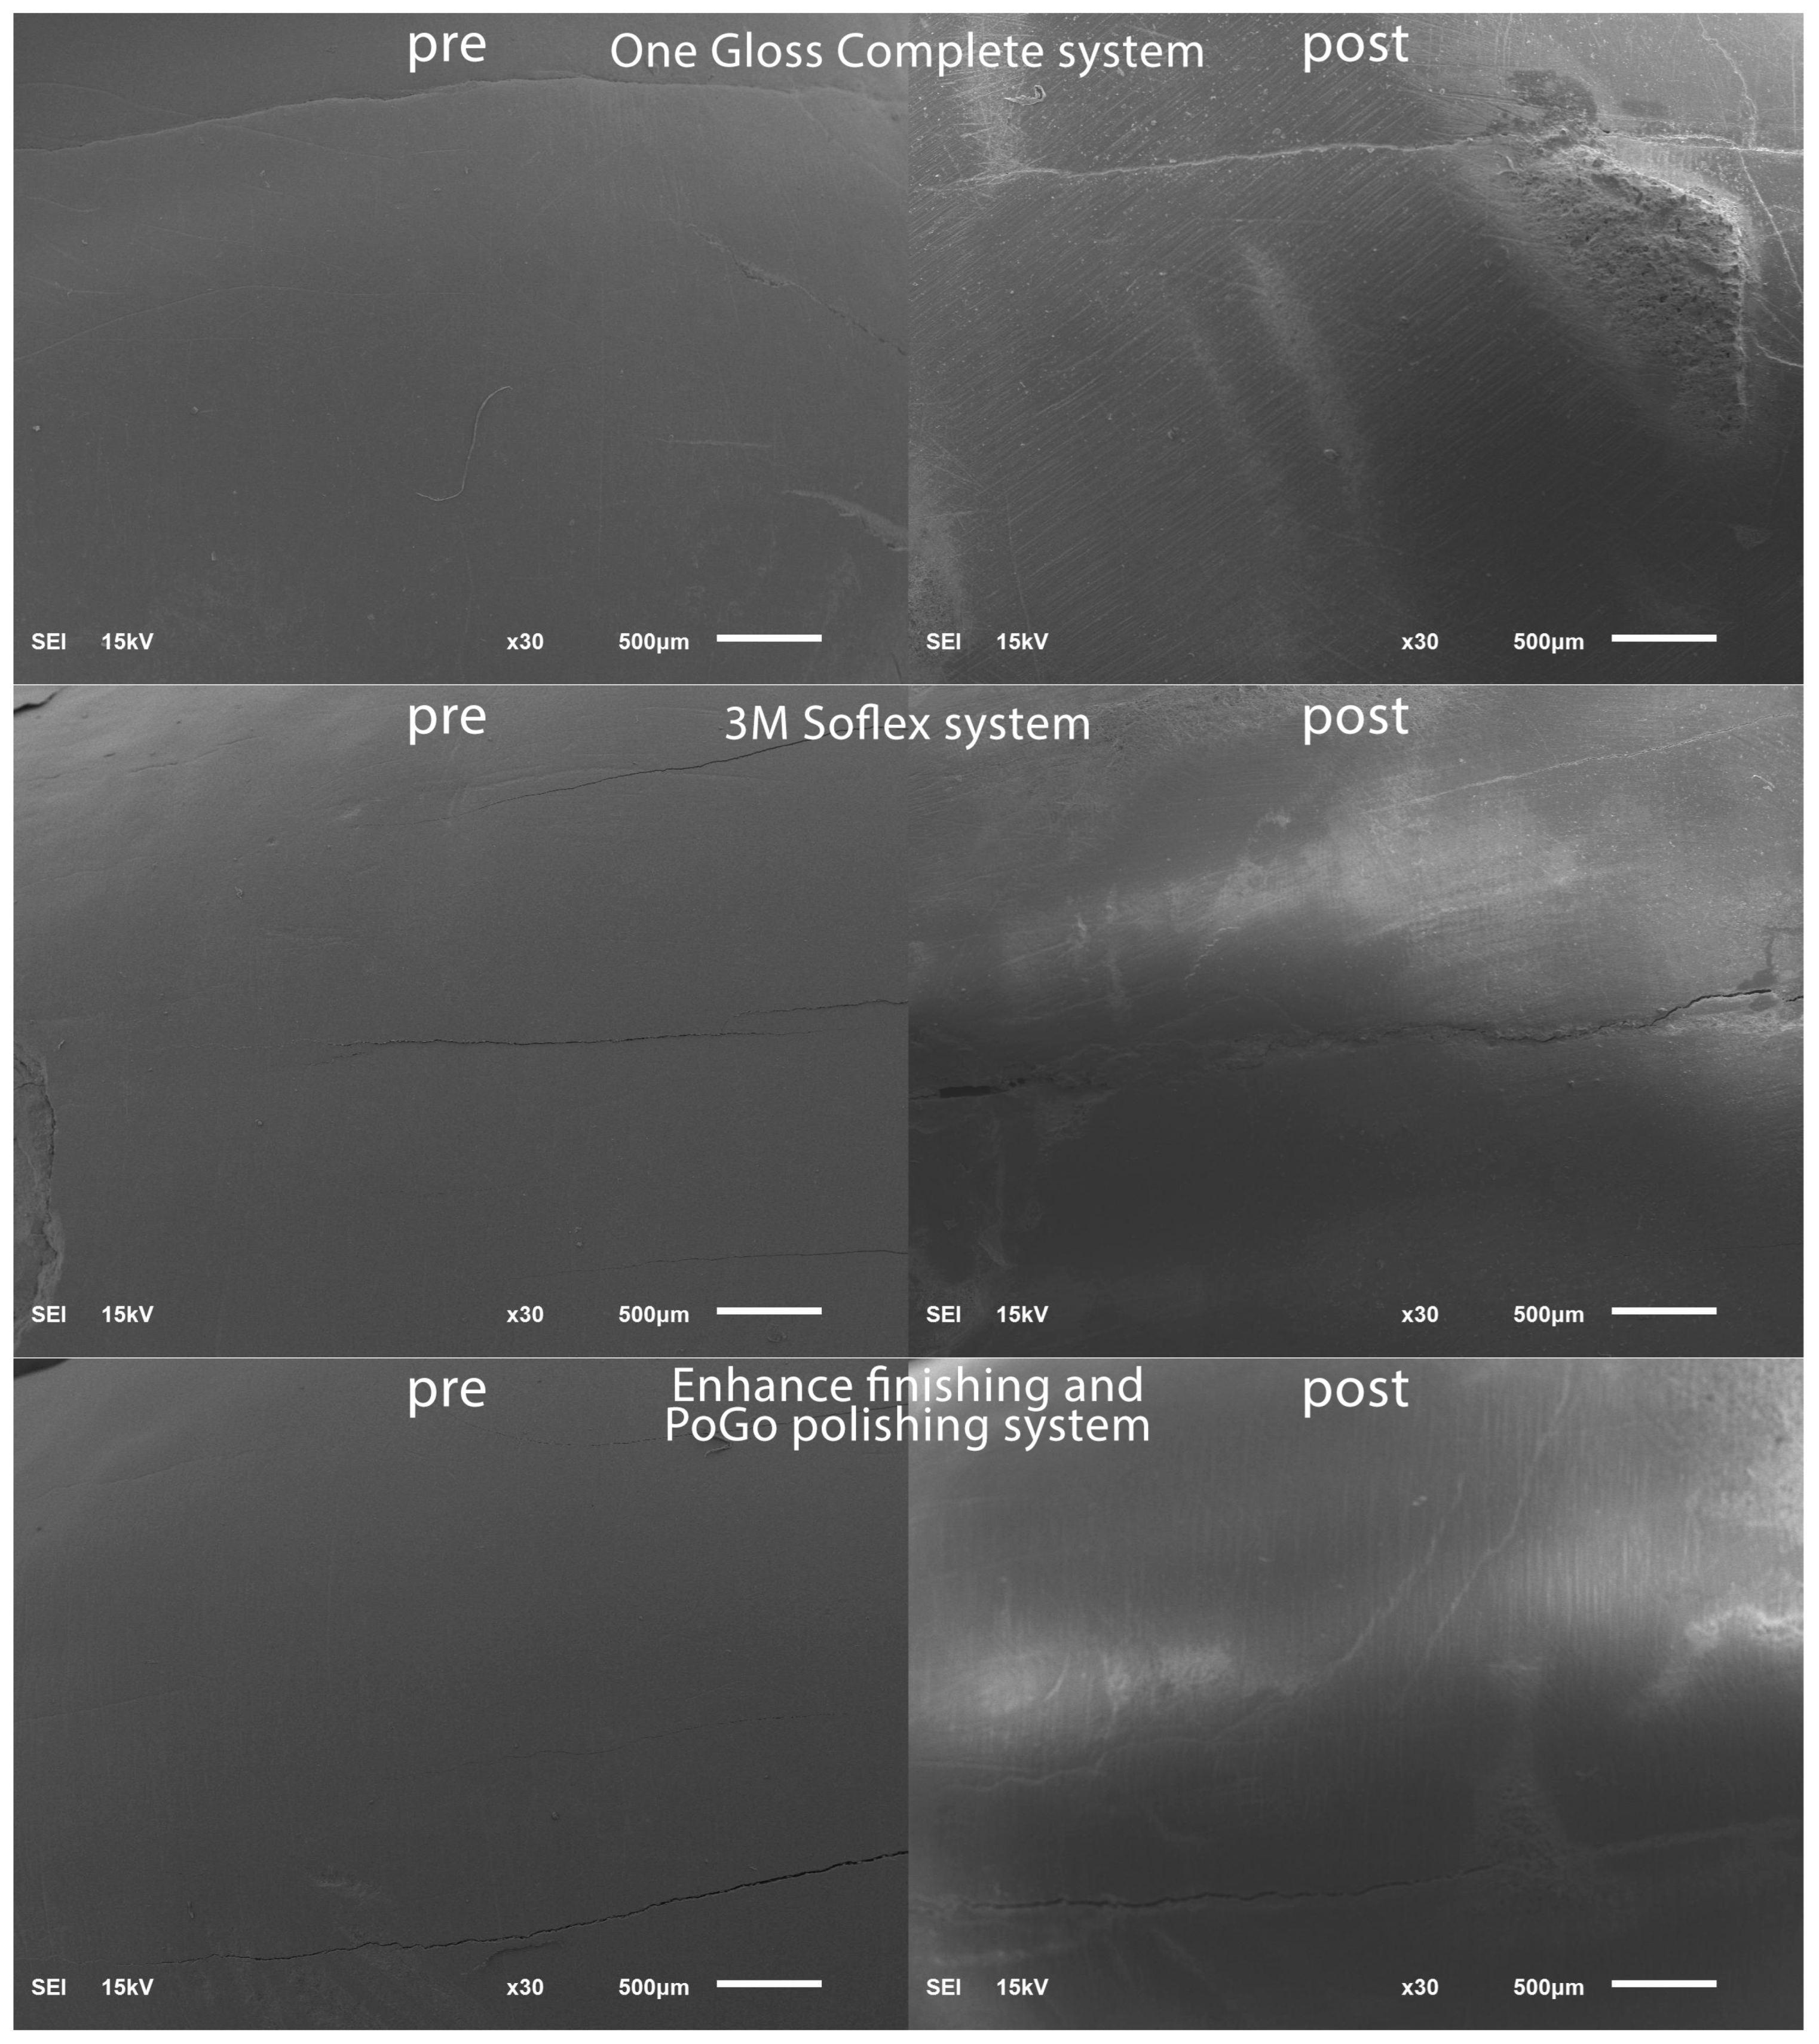

To establish a baseline for the surface roughness data, the teeth were positioned within a vinyl polysiloxane putty mold in preparation for scanning using a scanning electron microscope (SEM) (JSM 6610LV; Jeol, Tokyo, Japan). The SEM parameters employed included 15 kV voltage and a 10 mm working distance. To highlight specific regions of interest on the facial tooth surface, magnifications of 30× were chosen and representative SEM scans were captured in the pre-bracket bonding state; see Figure 1.

Figure 1.

SEM images pre-bracket bonding and post-bracket debonding.

Post-residual cement removal, enamel roughness measurements were performed in a similar routine to the pre-operative enamel surface roughness measurements and representative SEM scans were captured post-bracket debonding; see Figure 1.

Significant differences were noticed between the seven tested residual cement removal systems in terms of the surface roughness introduced into the enamel surface. The Sof-Lex system group demonstrated the smoothest post-finishing enamel surface. The Sof-Lex was found to significantly reduce surface roughness, as evidenced by the lowest enamel roughness measurements (2.335 μm), compared to the other tested methods. The Stainbuster system recorded the second lowest enamel roughness measurements (2.599 μm). The OneGloss system recorded the third lowest enamel roughness measurements (2.649 μm). Renew Finishing System Points recorded the fourth lowest enamel roughness measurements (3.299 μm). The Renew carbide bur system recorded the fifth lowest enamel roughness measurements (3.367 μm). The Enhance Finishing and PoGo Polishing system recorded the sixth lowest enamel roughness measurements (3.416 μm), whereas the Renew #129 diamond bur system was found to produce the highest levels of roughness on the enamel surface (4.716 μm), as evidenced by the surface profilometry and scanning electron microscopy (SEM) results. In related context, Bansal et al. [28] suggested that the Sof-Lex system ranked second after the Mylar matrix in terms of smoothing, while Shah et al. [24] reported that the Sof-Lex system also secured the second position, following the Enhance Finishing system.